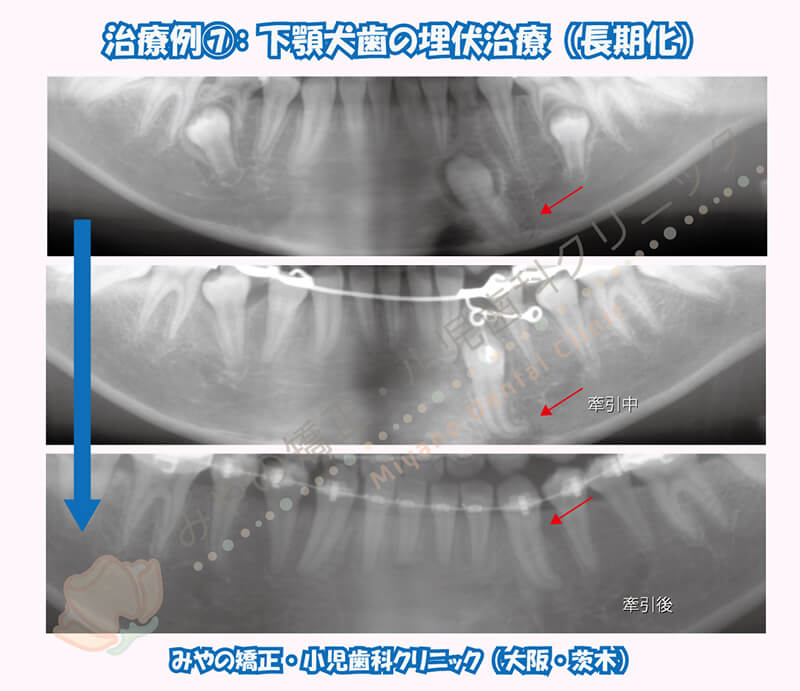

左下犬歯が埋伏しています。

先ほどの犬歯埋伏の診断のポイントと照らし合わせてみても、

①犬歯の向きや位置が正常の位置に比べて少し異なる場所に位置する

②犬歯の見え方が左右で異なる

③犬歯が本来の場所とは異なる場所や向きに位置している

が該当します。

年齢も高く、犬歯の根が完成しつつありましたが牽引治療を試みました。

埋まっている犬歯の根の形をみると根尖が90°曲がってしまっており、牽引方向に対し抵抗する形態をしていました。

元々の埋伏位置も深かったため、牽引だけで2年半程度かかり長期化しています。